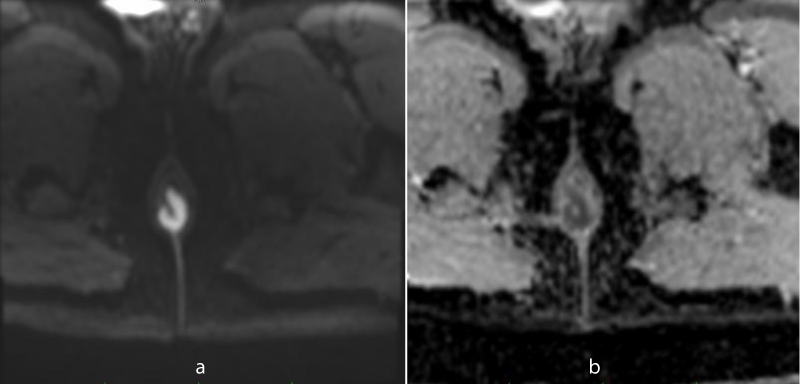

MR imaging revealed short segment circumferential wall thickening of the anal canal with lower margin approximately 1.7cm from anal verge. It was nearly 3 cm in length and 7mm in maximum thickness. The wall thickening showed hyperintense signal in T1-weighted images and T2-weighted images (Figures 1-3). Restricted diffusion with corresponding low signal in ADC map was noted figure 4. Post gadolinium T1-weighted fat saturated images showed hyper enhancement of the wall thickening (Figure 5). The thickening was involving the internal sphincter. No invasion of intersphincteric plane and external sphincter was noted. No extension into perianal fat was noted. Few enlarged heterogenously enhancing lymph nodes were noted in right inguinal region largest 23 x 21 mm in size. The patient underwent wide local excision with right inguinal dissection and adjuvant loco-regional radiotherapy. The histopathological examination showed features suggestive of primary anal malignant melanoma (Figure 6). In routine follow up, the patient showed no features of local recurrence or distant metastasis.

Figure 4: Restricted diffusion is seen in DW image (a) with corresponding low signal in ADC map (b).